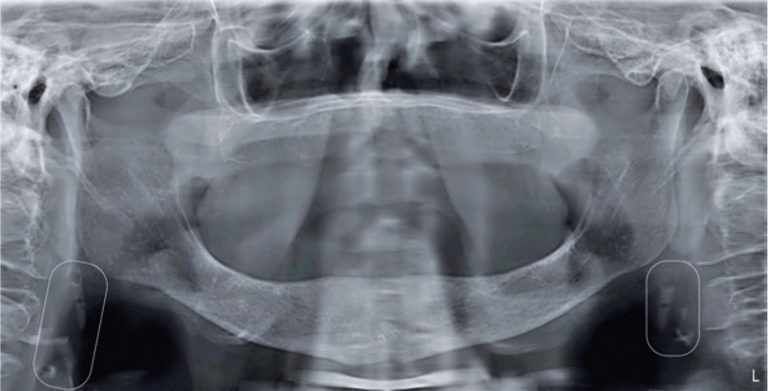

Relata-se o caso de uma paciente, do sexo feminino, 86 anos, que compareceu ao serviço de diagnóstico oral para avaliação de dor bucal. À oroscopia, não foram observadas lesões. Solicitou-se, então, uma RPO, na qual não foram observadas alterações associadas à queixa principal. Entretanto, observaram-se calcificações difusas na proximidade das vértebras C3 e C4, bilateralmente (). Diante desses achados, as hipóteses foram ateroma calcificado em carótida, cartilagem tritícea e linfonodos calcificados. Em virtude da hipótese de ateroma calcificado nas carótidas, solicitou-se ultrassonografia com Doppler colorido e pulsado que demonstrou carótidas comuns com espessura mediointimal aumentada, bulbos carotídeos com placas ateromatosas com estenose menor que 50% () e carótidas internas com placas ateromatosas com sinais de estenose entre 50% a 69%, bilateralmente. A paciente foi encaminhada para avaliação cardiológica e encontra-se em acompanhamento médico. Portanto, destaca-se a importância da observação de radiopacidades na topografia da artéria carótida em RPO e sua posterior definição diagnóstica, visando à prevenção do AVC.